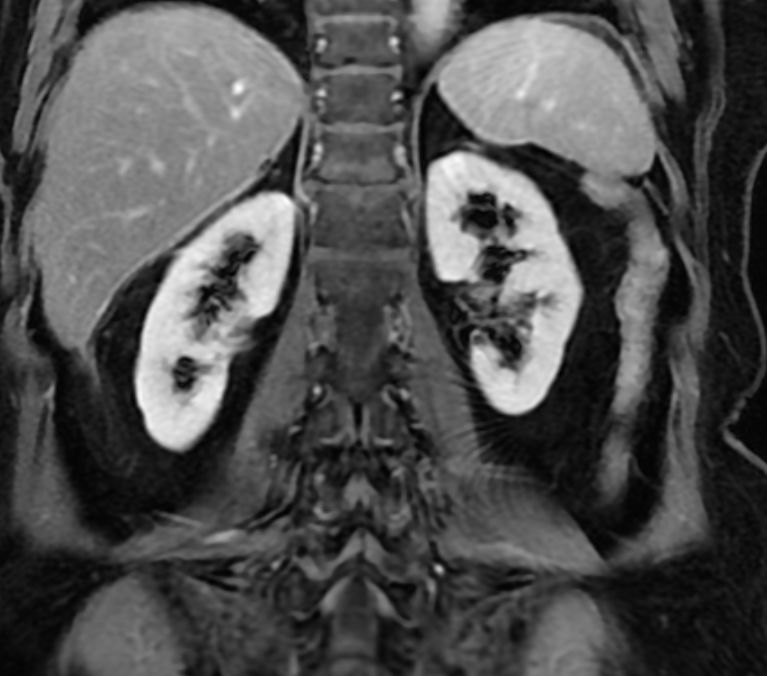

КТ ретроперитонеального фиброза: Изображения и диагностика